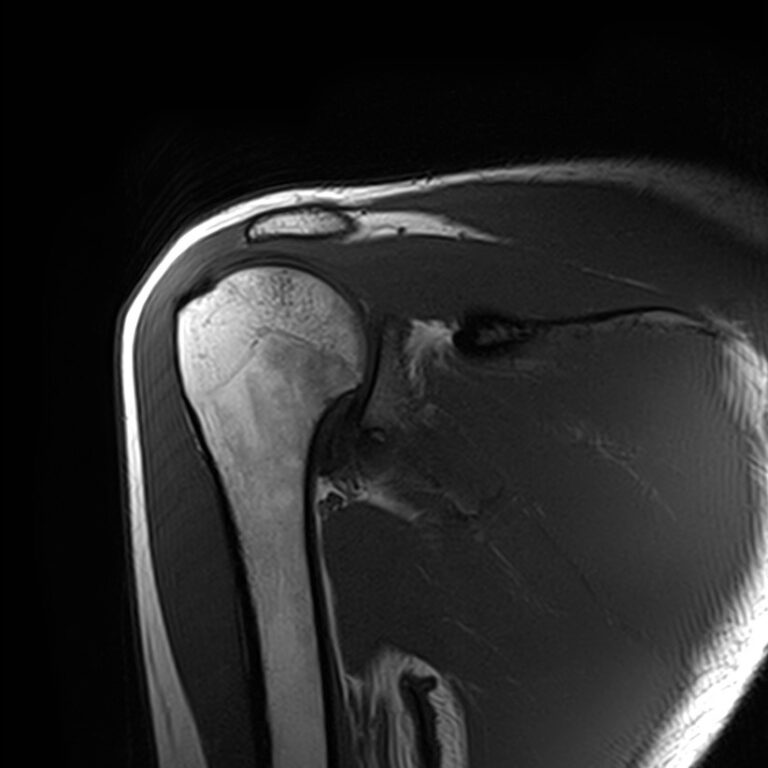

Плечевой сустав является наиболее подвижным сочленением, которое образовано лопаткой и головкой плечевой кости. У сустава нет мощных связок, он укрепляется мышцами плечевого пояса, окружающими его по типу корсета. Суставную капсулу образуют короткие связки, расположенные вокруг сустава. Благодаря такому строению сустав отличается высокой подвижностью, но при этом склонностью к вывихам. Полость сустава заполнена синовиальной жидкостью, питающей хрящи и служащей смазкой для них.

Метод МРТ позволяет оценить состояние всех анатомических областей плечевого сустава,  включая костную структуру, суставную капсулу, полость сустава с выстилающей его синовиальной оболочкой, связки, сухожилия, мышцы и окружающие мягкие ткани.

• Дегенеративно-дистрофические заболевания, в частности деформирующий остеоартроз, при котором происходит истончение хряща на фоне нарушения его питания. В результате развивается дисфункция сустава и деформация костных структур.

• Воспалительные заболевания с поражением как самого сустава (артрит), так и окружающих мягких тканей (синовит, бурсит, тендовагинит).

• Развитие в области плечевого сустава как доброкачественных, так и злокачественных новообразований. Поражение сустава может быть первичной опухолью, исходящей из костной ткани или мягких тканей, либо за счет метастазирования из отдаленных очагов.

• Травмы плечевого сустава, различные переломы, при этом наиболее часто встречаются вывихи, что обусловлено анатомией сустава. Нередко травмы сустава с разрывом связок и сухожилий ведут в дальнейшем к развитию нестабильности плечевого сустава и могут стать причиной формирования привычных вывихов.